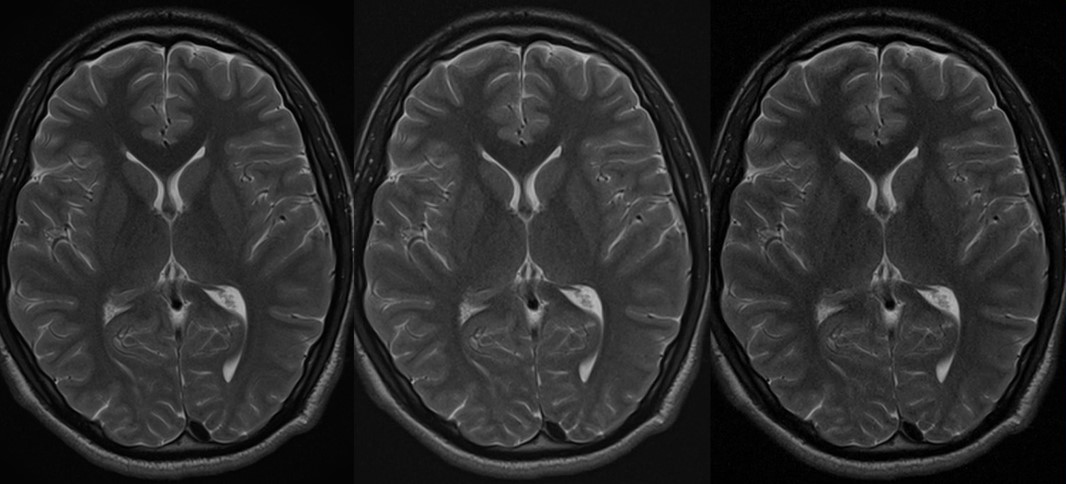

Original

Compressed SPEEDER 2.0

Compressed SPEEDER 2.5

Время сканирования 3:10

Vantage Orian 1.5T

Время сканирования 1:46

Vantage Orian 1.5T

Время сканирования 1:18

Vantage Orian 1.5T